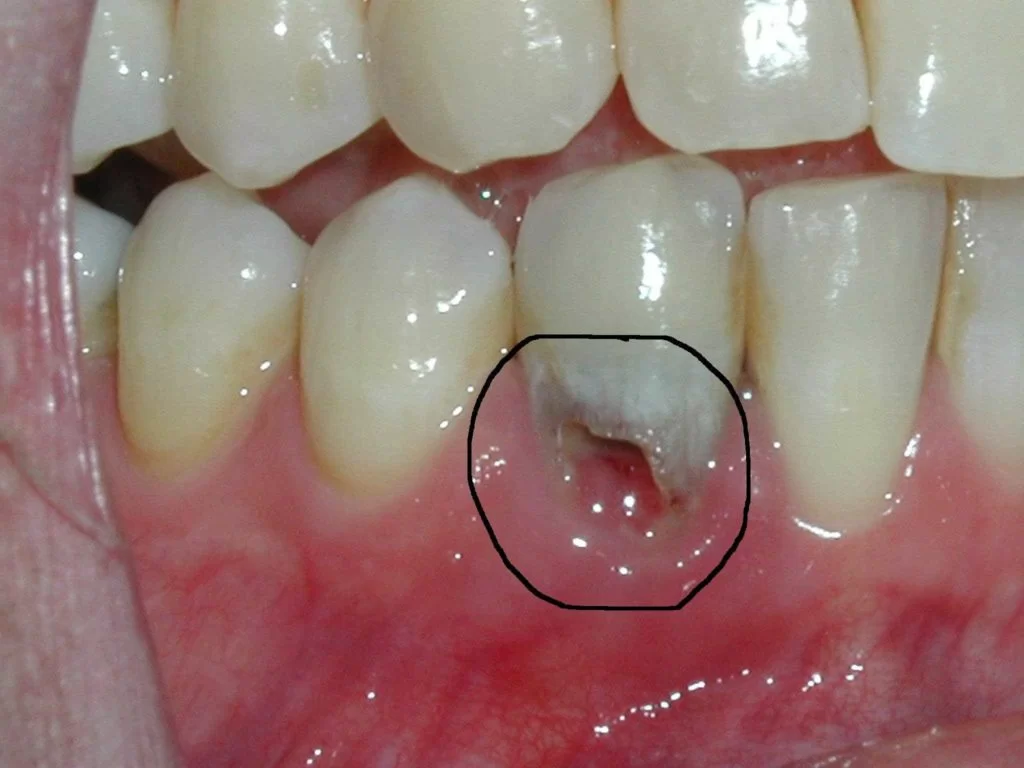

Tiêu xương chân răng

Tiêu xương răng (hay còn gọi là loãng xương) là tình trạng xương trở nên mỏng và yếu hơn bình thường. Điều này thường xảy ra khi lượng khoáng chất trong xương giảm đi hoặc khi quá trình hấp thu khoáng chất của cơ thể bị suy giảm.

Tiêu xương răng có thể gây ra nhiều vấn đề, bao gồm dễ gãy xương, đau đớn và sưng tấy. Nếu không được chữa trị kịp thời, tiêu xương răng có thể dẫn đến các vấn đề nghiêm trọng hơn như loãng xương toàn thân và các chấn thương liên quan đến xương.

Ghép xương răng trong quá trình trồng răng Implant là một tiểu phẫu nhằm bổ sung, tái tạo phần xương hàm đã bị tiêu đi trong thời gian răng bị mất, giúp tăng thể tích xương hàm, tạo tiền đề để lắp trụ Implant thành công.